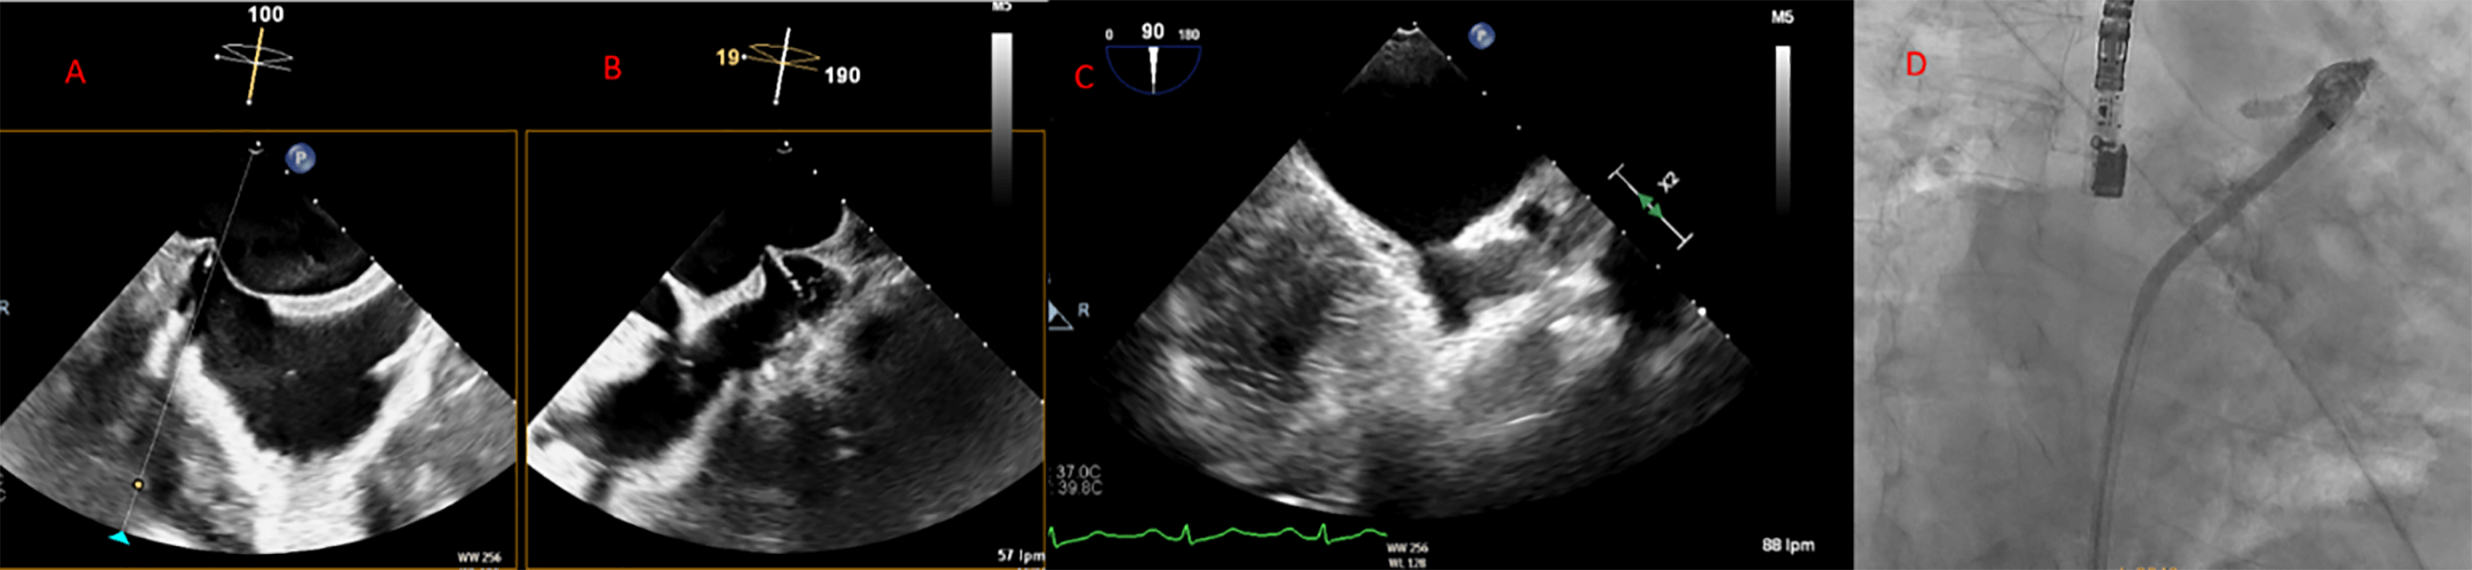

Fig. 7.

Transseptal puncture (TSP) using the VersaCross system. The Versacross wire, within its sheath, is seen in contact with the interatrial septum under fluoroscopy (left). Transesophageal echocardiography (TEE) reveals tenting at the level of fossa ovalis and the wire crossing into the left atrium (middle), where it immediately assumes a pigtail shape (right), providing a safe means of crossing the septum.